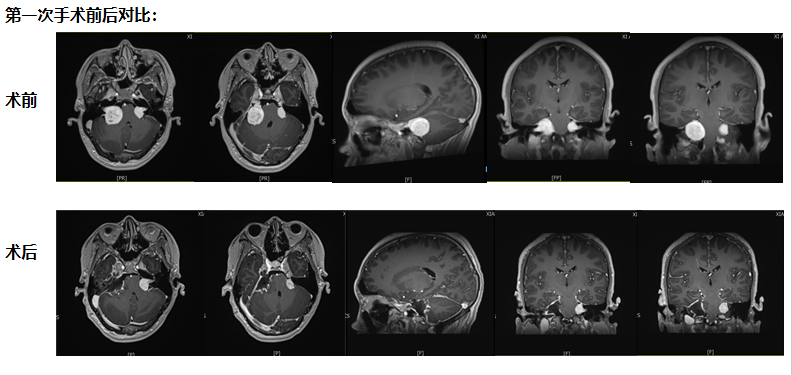

第一次手术:从耳后开口 既要拆瘤又要保听力

考虑到小倪才21岁,团队没选 “一刀切” 的方案,而是决定从耳后开一个约10厘米的小口 —— 这个位置能精准摸到耳朵旁边的肿瘤,还能尽量避开控制听力、面部活动的神经。

手术当天,医生在显微镜下一点点 “剥” 肿瘤:剥到肿瘤深处时,医生发现再往里切,必然会伤着听力神经。“停!这里留一点点,先保听力。” 团队果断调整,把能安全切除的肿瘤全清干净,再仔细止血,避免术后出血。